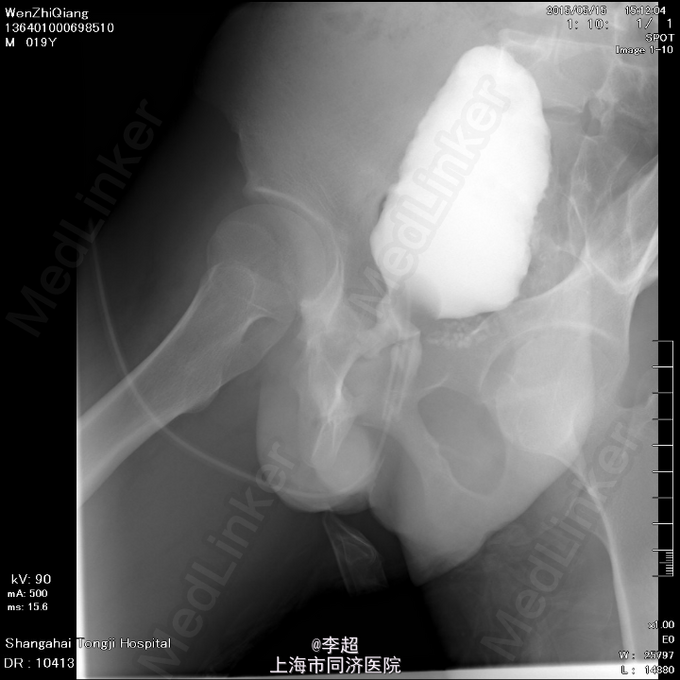

查体 辅查

患者尿道开口于阴囊下,会阴部,无法控尿,尿液自行流出 尿道造影仅显示假道,正常尿道仅存留阴茎短尿道,约5cm长

择期行耻骨下缘切除+阴囊皮瓣代尿道成形+尿道膀胱拖入术 手术过程:行会阴部倒Y形切口切口,切口包括会阴部尿道造口处,术中见阴茎部尿道存在尿道-阴茎皮肤瘘道,予切除瘘道。分离后尿道,探查见后尿道疤痕明显,并且于耻骨相连,局部粘连严重。考虑有假道存在可能,遂做耻骨上纵行切口4cm,探查膀胱发现距目前尿道口处1cm处前方存在另一内口,为盲道,盲端被变形耻骨完全遮挡。遂使用骨刀劈凿穿耻骨并切除耻骨下缘,凿通至膀胱盲道,将盲端断断显露,使用膀胱镜探查盲道,见盲端口膀胱肌肉括约功能较好,推断为真性尿道,使用左侧阴囊及大腿根部皮瓣约8cm*3cm大小,分离皮瓣下组织血管形成血管蒂,翻转皮瓣形成尿道,将皮瓣尿道近端拖入膀胱,与真性尿道膀胱黏膜处直针缝合。另将皮瓣尿道远端与阴茎部正常尿道粘膜缝合,留置F14号导尿管,假道处尿道予留置Foley14导尿管。